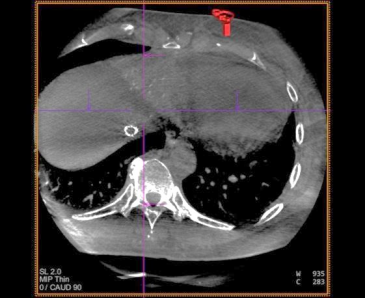

术中 CBCT 可见肝左内叶肿瘤强化病灶

CBCT 扫描血管重建可见,血管迂曲及靶病灶大小和位置

栓塞结束后 CBCT 扫描,原肝左内叶病灶无强化